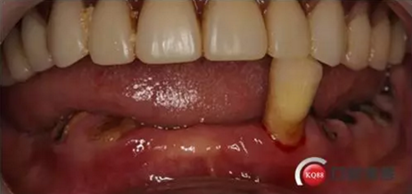

病例簡(jiǎn)介:患者:李女士,71歲

下頜假牙戴不穩(wěn),要求固定修復(fù);

現(xiàn)病史:下頜假牙戴了多年,最近有顆牙脫落戴不穩(wěn)求診

檢查:上頜無(wú)牙頜假牙穩(wěn)定性尚可,下頜3435364243殘根;33殘冠1-2度松動(dòng),其他牙齒缺失;CBCT檢查:下頜牙槽骨前牙區(qū)骨高度足,后牙區(qū)骨高度最低為8mm,骨寬度足。